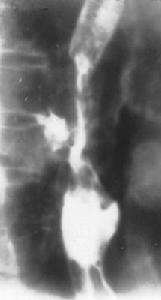

(2)分期方法:對肛管癌的分期有多種方法,但尚無一種統一的分期方法。臨床分期主要依據術後腫瘤浸潤深度判定;超聲分期(1991年提出)主要依據超聲重建圖像,並根據腫瘤大小、體積和肛周淋巴結情況判定侵犯深度;IUAC/AJCC標準認為肛門邊緣區的腫瘤屬於皮膚癌。

超聲內鏡(EUS)能夠了解病變侵犯深度以及周圍淋巴結情況。依據外科手術判斷腫瘤浸潤深度往往受組織水腫和炎症程度的影響,可能會有一定誤差,而EUS對於判斷分期比較準確,且可測量出淋巴結的大小如果淋巴結大於1cm可認為是轉移的表現。另外,對腫大的淋巴結也可進行EUS下細針穿刺活檢。

儘管EUS多用於分期研究,但為了使分期更加準確,有時需要依據其他檢查如經陰道的超聲檢查對於判斷直腸陰道壁是否受侵犯有重要意義

肛周腫瘤——表5腹部和盆腔CT有助於了解肝臟盆腔器官、髂內淋巴結等是否有轉移。MRI較CT更為準確。另外,胸部X線檢查有時也是必需的。